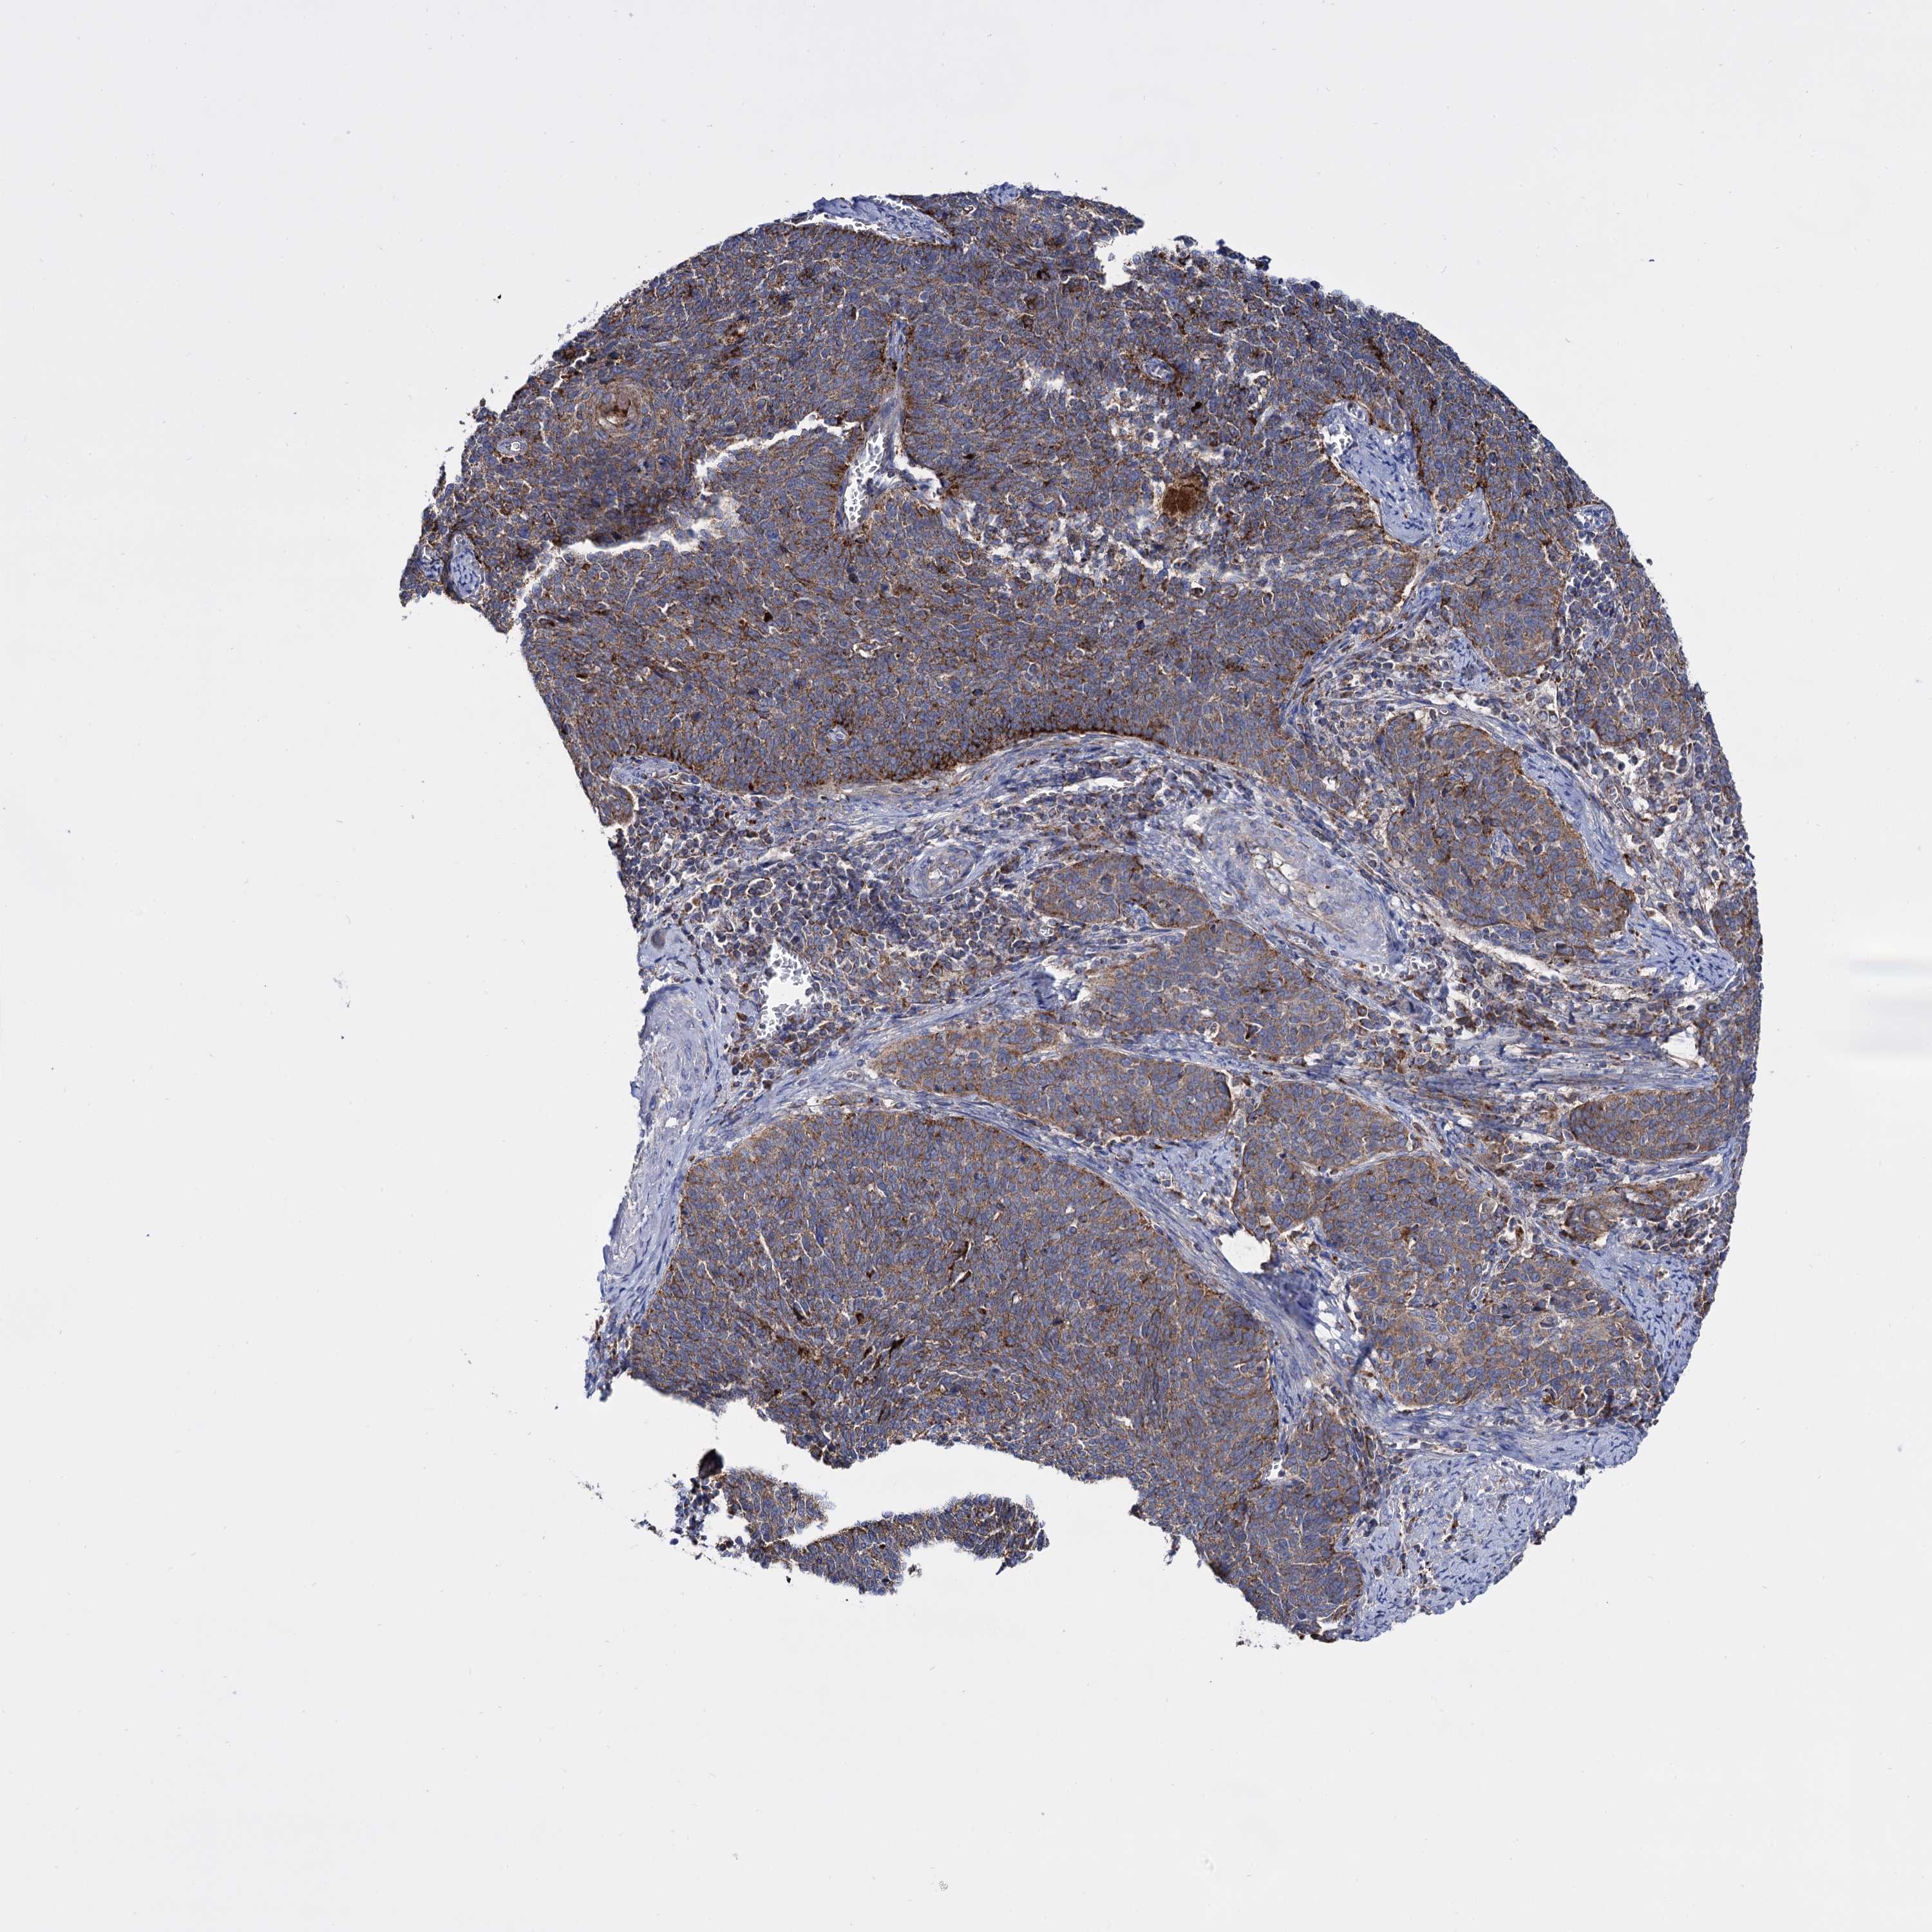

CERVICAL CANCER - Protein expressioni

A mouse-over function shows sample information and annotation data. Click on an image to view it in a full screen mode. Samples can be filtered based on level of antibody staining by selecting one or several of the following categories: high, medium, low and not detected. The assay and annotation is described here.

Note that samples used for immunohistochemistry by the Human Protein Atlas do not correspond to samples in the TCGA dataset.

Antibody stainingi

Antibody staining in the annotated cell types in the current human tissue is reported as not detected, low, medium, or high, based on conventional immunohistochemistry profiling in selected tissues. This score is based on the combination of the staining intensity and fraction of stained cells.

Each image is clickable and will lead to virtual microscopy that enables deeper exploration of all samples and also displays staining intensity scores, fraction scores and subcellular localization as well as patient and tissue information for each sample.

Antibody HPA040845

Staining

High

Medium

Low

Not detected

Intensity

Strong

Moderate

Weak

Negative

Quantity

>75%

75%-25%

<25%

None

Location

Nuclear

Cytoplasmic/membranous

Cytoplasmic/membranous,nuclear

Squamous cell carcinoma, NOS

Adenocarcinoma, NOS